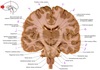

9

Q

a

Body of corpus callosum

10

b

septum pellucidum

11

c

Corona radiata

12

d

Anterior horn of lateral ventricle

13

e

Globus pallidus

14

f

Anterior commissure

15

g

Optic chiasm

16

h

Optic tract

17

i

Uncus

18

j

19

k

20

L

Putamen

21

m

Anterior limb of internal capsule

22

n

Head of caudate nucleus